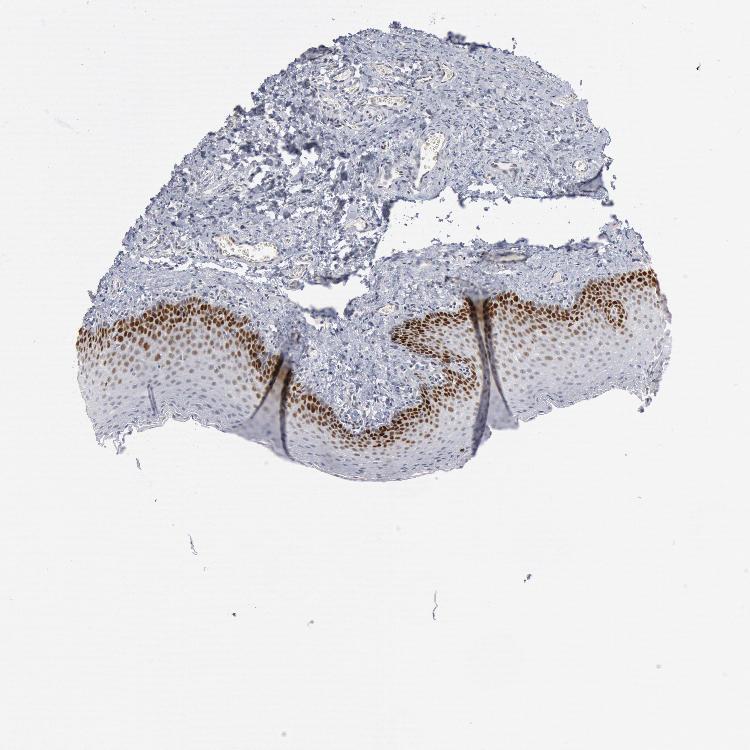

TISSUE PRIMARY DATA ORAL MUCOSA Show tissue menu

ORAL MUCOSA - Antibody stainingi

Antibody staining in the annotated cell types in the current human tissue is reported as not detected, low, medium, or high, based on conventional immunohistochemistry profiling in selected tissues. This score is based on the combination of the staining intensity and fraction of stained cells.

Each image is clickable and will lead to virtual microscopy that enables deeper exploration of all samples and also displays staining intensity scores, fraction scores and subcellular localization as well as patient and tissue information for each sample.

Antibody HPA001122

Squamous epithelial cells Medium